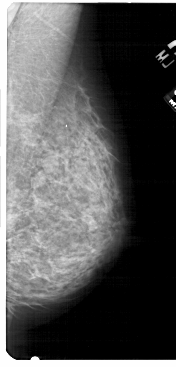

A_1755_1.RIGHT_CC

RIGHT_CC LINES 4966 PIXELS_PER_LINE 2356 BITS_PER_PIXEL 12 RESOLUTION 43.5 NON_OVERLAY